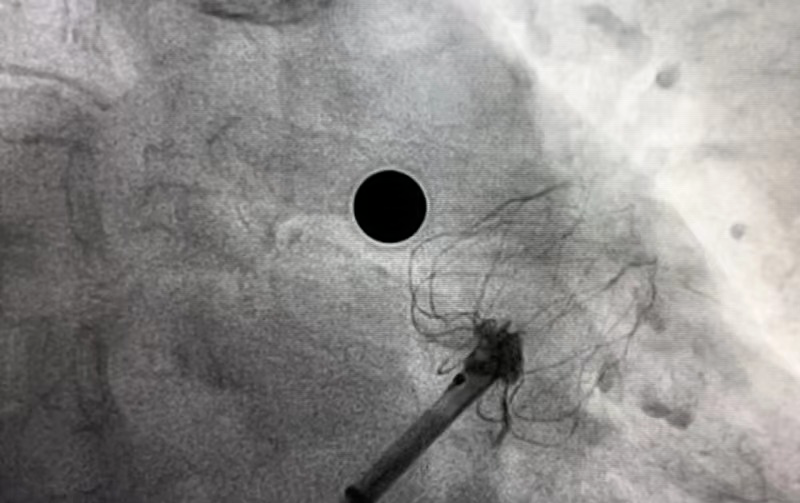

经过完善的术前CT和全面的Truplan软件术前分析准备。在介入室的全面配合下完成该患者的术前准备工作,谢桂庭进行房间隔穿刺,精准定位穿刺位点。行左心耳造影,造影结果显示开口28mm左右,深度32mm左右。结合术前Truplan结果以及术中DSA测量结果,选用WATCHMAN 33mm封堵器进行封堵。

在团队紧密配合下,谢桂庭巧妙地将封堵器坐落到心耳上缘囊袋,同时施加逆时针的力减少下缘露肩。缓慢平稳展开,一次到位,实现平口封堵。在DSA下进行牵拉实验,封堵器回弹明显无位移,提示稳定性良好。左心耳封堵器无露肩,无残余分流,压缩比13%-25%,满足PASS原则评估,释放封堵器。